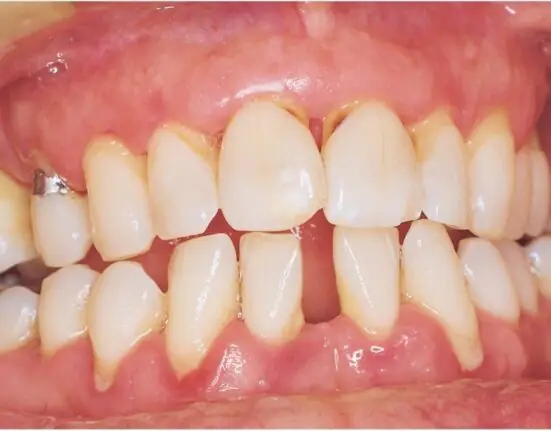

Periodontitis currently is treated via infection-fighting methods, molecules known as growth factors that promote tissue growth, and tissue regeneration using autologous mesenchymal stem cells (MSC) or a patient’s own bone marrow stem cells that belong to skeletal tissues such as cartilage, bone, and fat.

The ultimate goal of periodontal disease treatment is the reorganization of functional tissue that can regenerate the tissue that has been lost due to disease. However, the side effects of current regenerative treatments have been limited depending on age, systemic disease, and tissue quality and, as such, have been associated with severe defects.